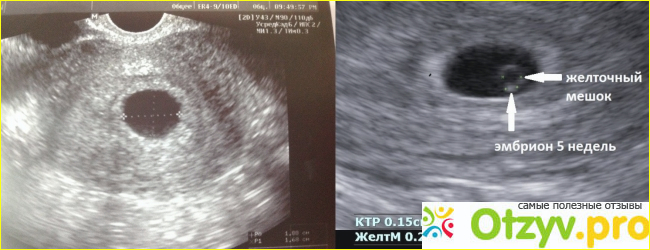

Сегодня, благодаря развитию медицины, появлению инновационных ультразвуковых сканеров распознать замершую беременность очень легко и это состояние превратилось в диагноз. Считается, что в мире более сорока процентов женщин когда-либо имели замершую-беременность, а это достаточно большой процент. При замершей беременности, выкидыш обычно происходит на первых неделях.